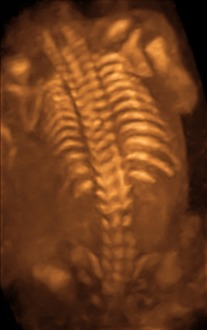

Open spina bifida can usually be detected during pregnancy by fetal ultrasound. Increased levels of maternal serum alpha-fetoprotein (MSAFP) should be followed up by two tests – an ultrasound of the fetal spine and amniocentesis of the mother's amniotic fluid (to test for alpha-fetoprotein and acetylcholinesterase). AFP tests are now mandated by some state laws (including California) and failure to provide them can have legal ramifications. In one case, a man born with spina bifida was awarded a $2-million settlement after court found his mother's OBGYN negligent for not performing these tests.[57] Spina bifida may be associated with other malformations as in dysmorphic syndromes, often resulting in spontaneous miscarriage. In the majority of cases, though, spina bifida is an isolated malformation.

Genetic counseling and further genetic testing, such as amniocentesis, may be offered during the pregnancy, as some neural tube defects are associated with genetic disorders such as trisomy 18. Ultrasound screening for spina bifida is partly responsible for the decline in new cases, because many pregnancies are terminated out of fear that a newborn might have a poor future quality of life. With modern medical care, the quality of life of patients has greatly improved.[53]